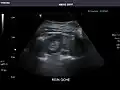

Abdominal ultrasonography (also called abdominal ultrasound imaging or abdominal sonography) is a form of medical ultrasonography (medical application of ultrasound technology) to visualise abdominal anatomical structures. It uses transmission and reflection of ultrasound waves to visualise internal organs through the abdominal wall (with the help of gel, which helps transmission of the sound waves). For this reason, the procedure is also called a transabdominal ultrasound, in contrast to endoscopic ultrasound, the latter combining ultrasound with endoscopy through visualize internal structures from within hollow organs.

Abdominal ultrasound can be used to diagnose abnormalities in various internal organs, such as the kidneys,[1] liver, gallbladder, pancreas, spleen and abdominal aorta. If Doppler ultrasonography is added, the blood flow inside blood vessels can be evaluated as well (for example, to look for renal artery stenosis). It is commonly used to examine the uterus and fetus during pregnancy; this is called obstetric ultrasonography.[2][3]

Advantages of ultrasound imaging of abdominal structures are that the procedure can be performed quickly, bed-side, involves no exposure to X-rays (which makes it useful in pregnant patients, for example) and is inexpensive compared to other often-used techniques such as computed tomography (CT scan) of the abdomen. Disadvantages are troublesome imaging if a lot of gas is present inside the bowels, if there is a lot of abdominal fat, and that the quality of the imaging depends on the experience of the person performing it.